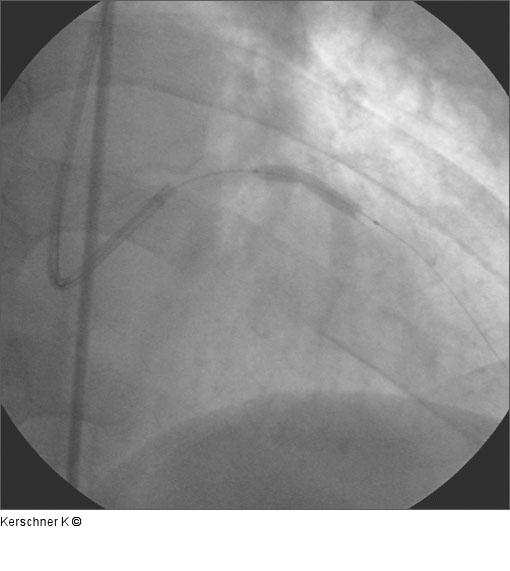

Abbildung 7: Stentimplantation - LAD Stentimplantation LAD / R. diagonalis in Crush-Technik. LAD Taxus Express 2 - 3,0 / 28 mm, 14 atm. |

Stentimplantation LAD / R. diagonalis in Crush-Technik. LAD Taxus Express 2 - 3,0 / 28 mm, 14 atm. |